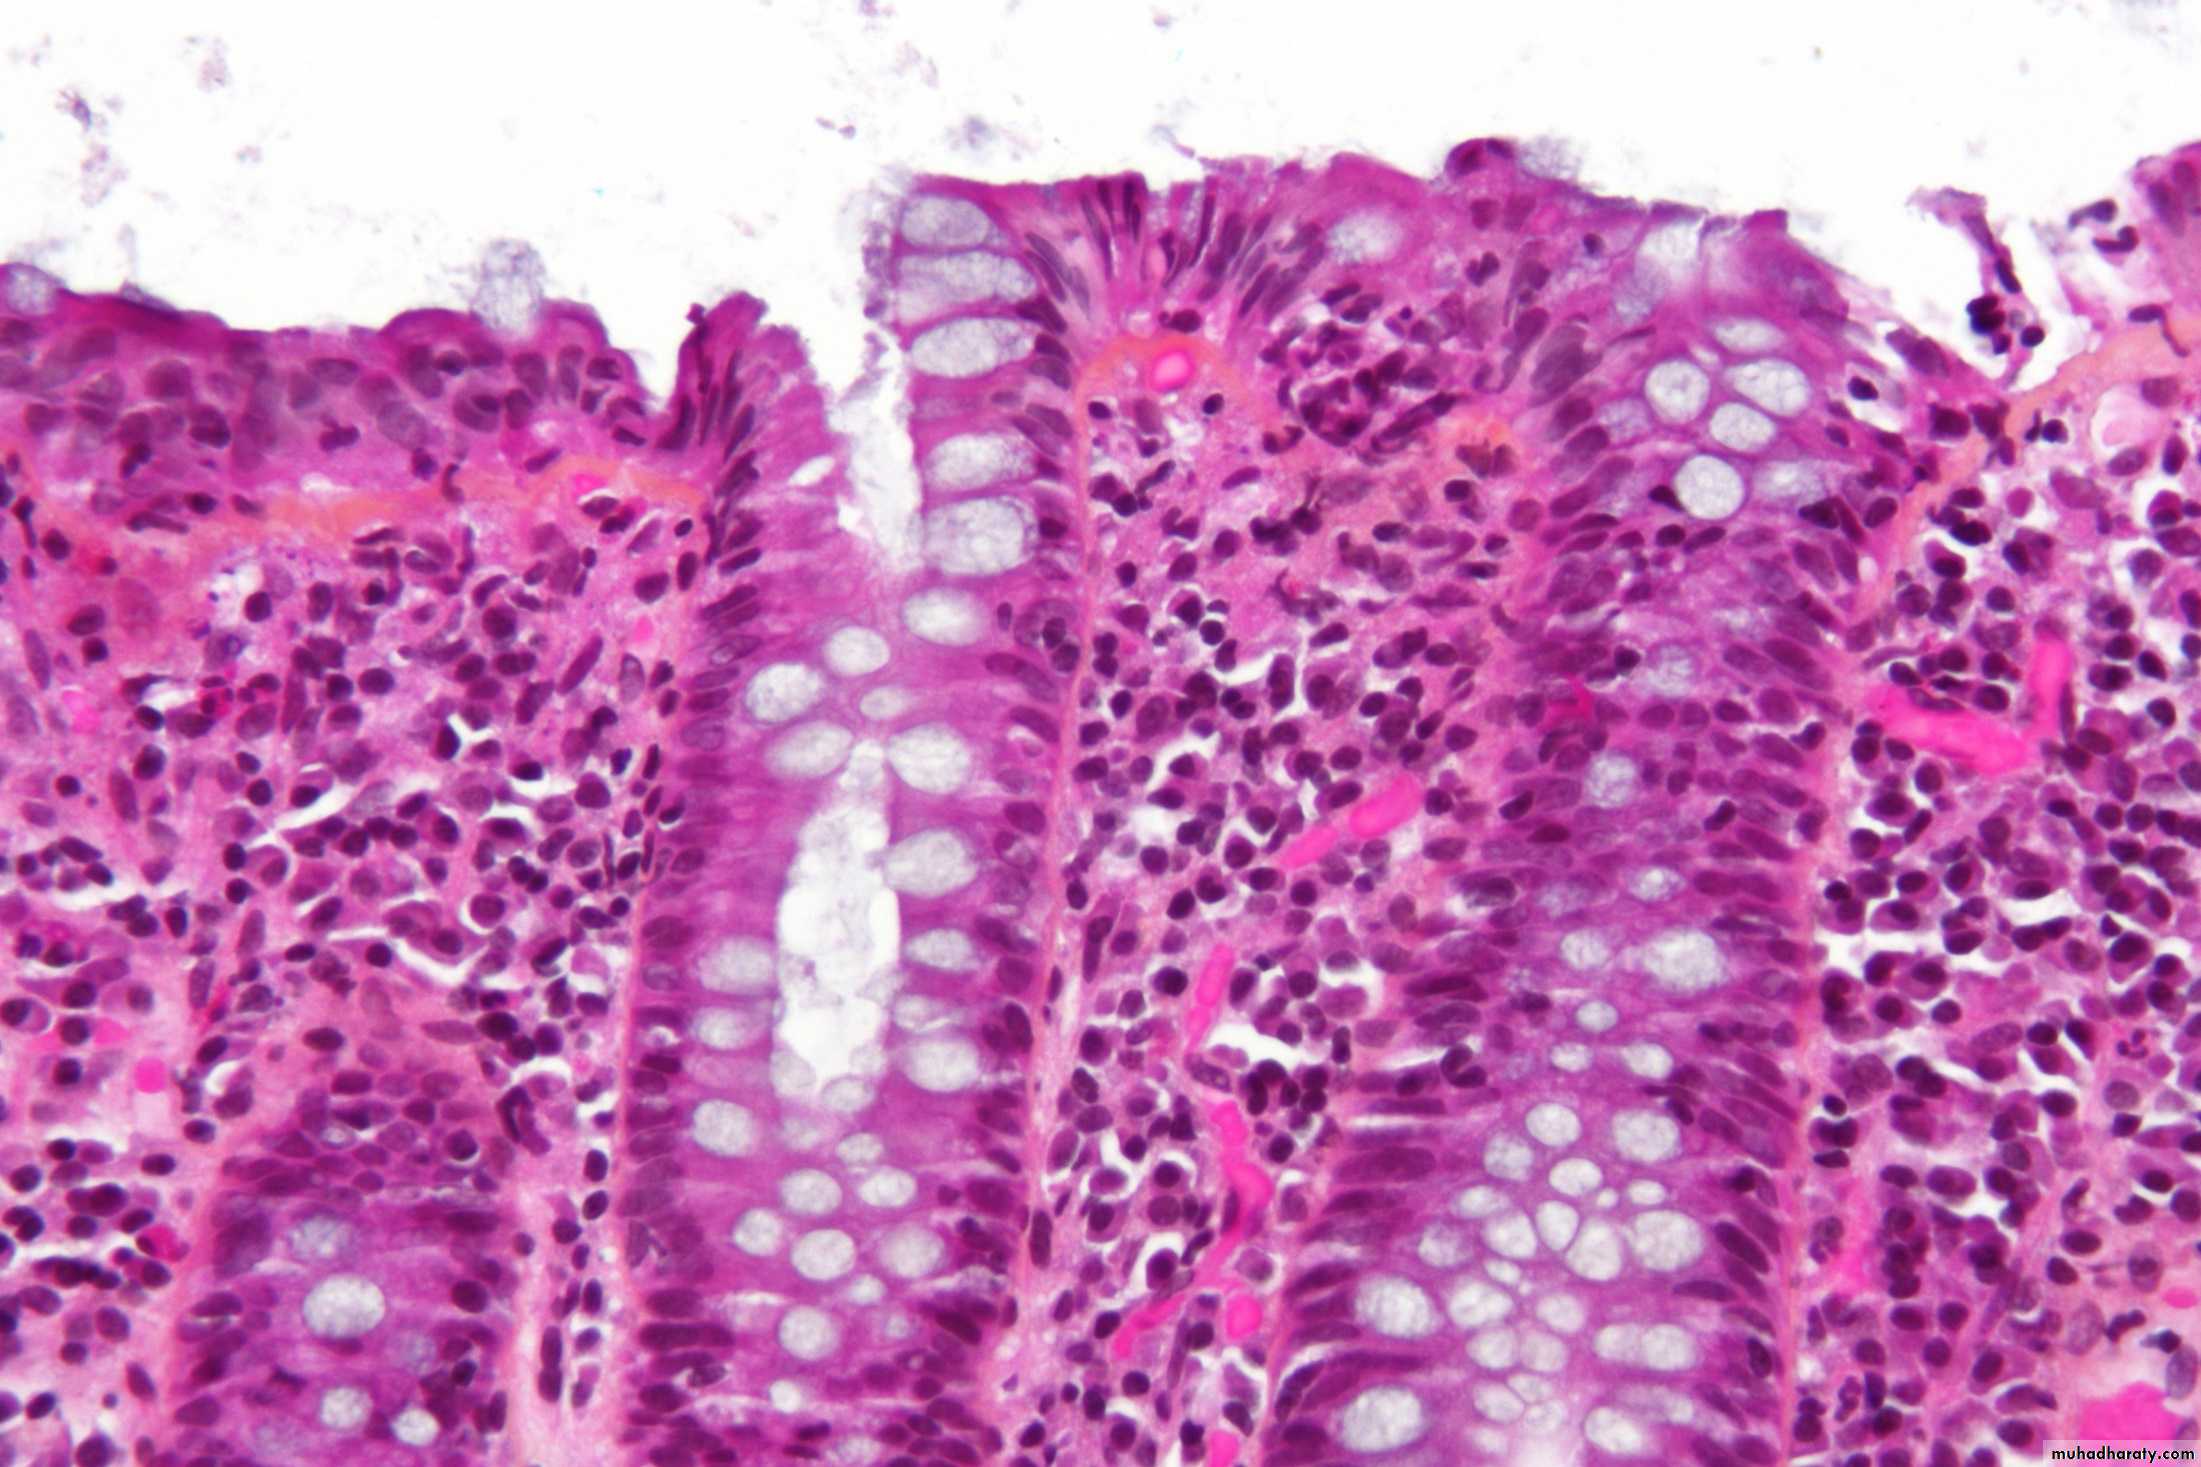

Normal appendix